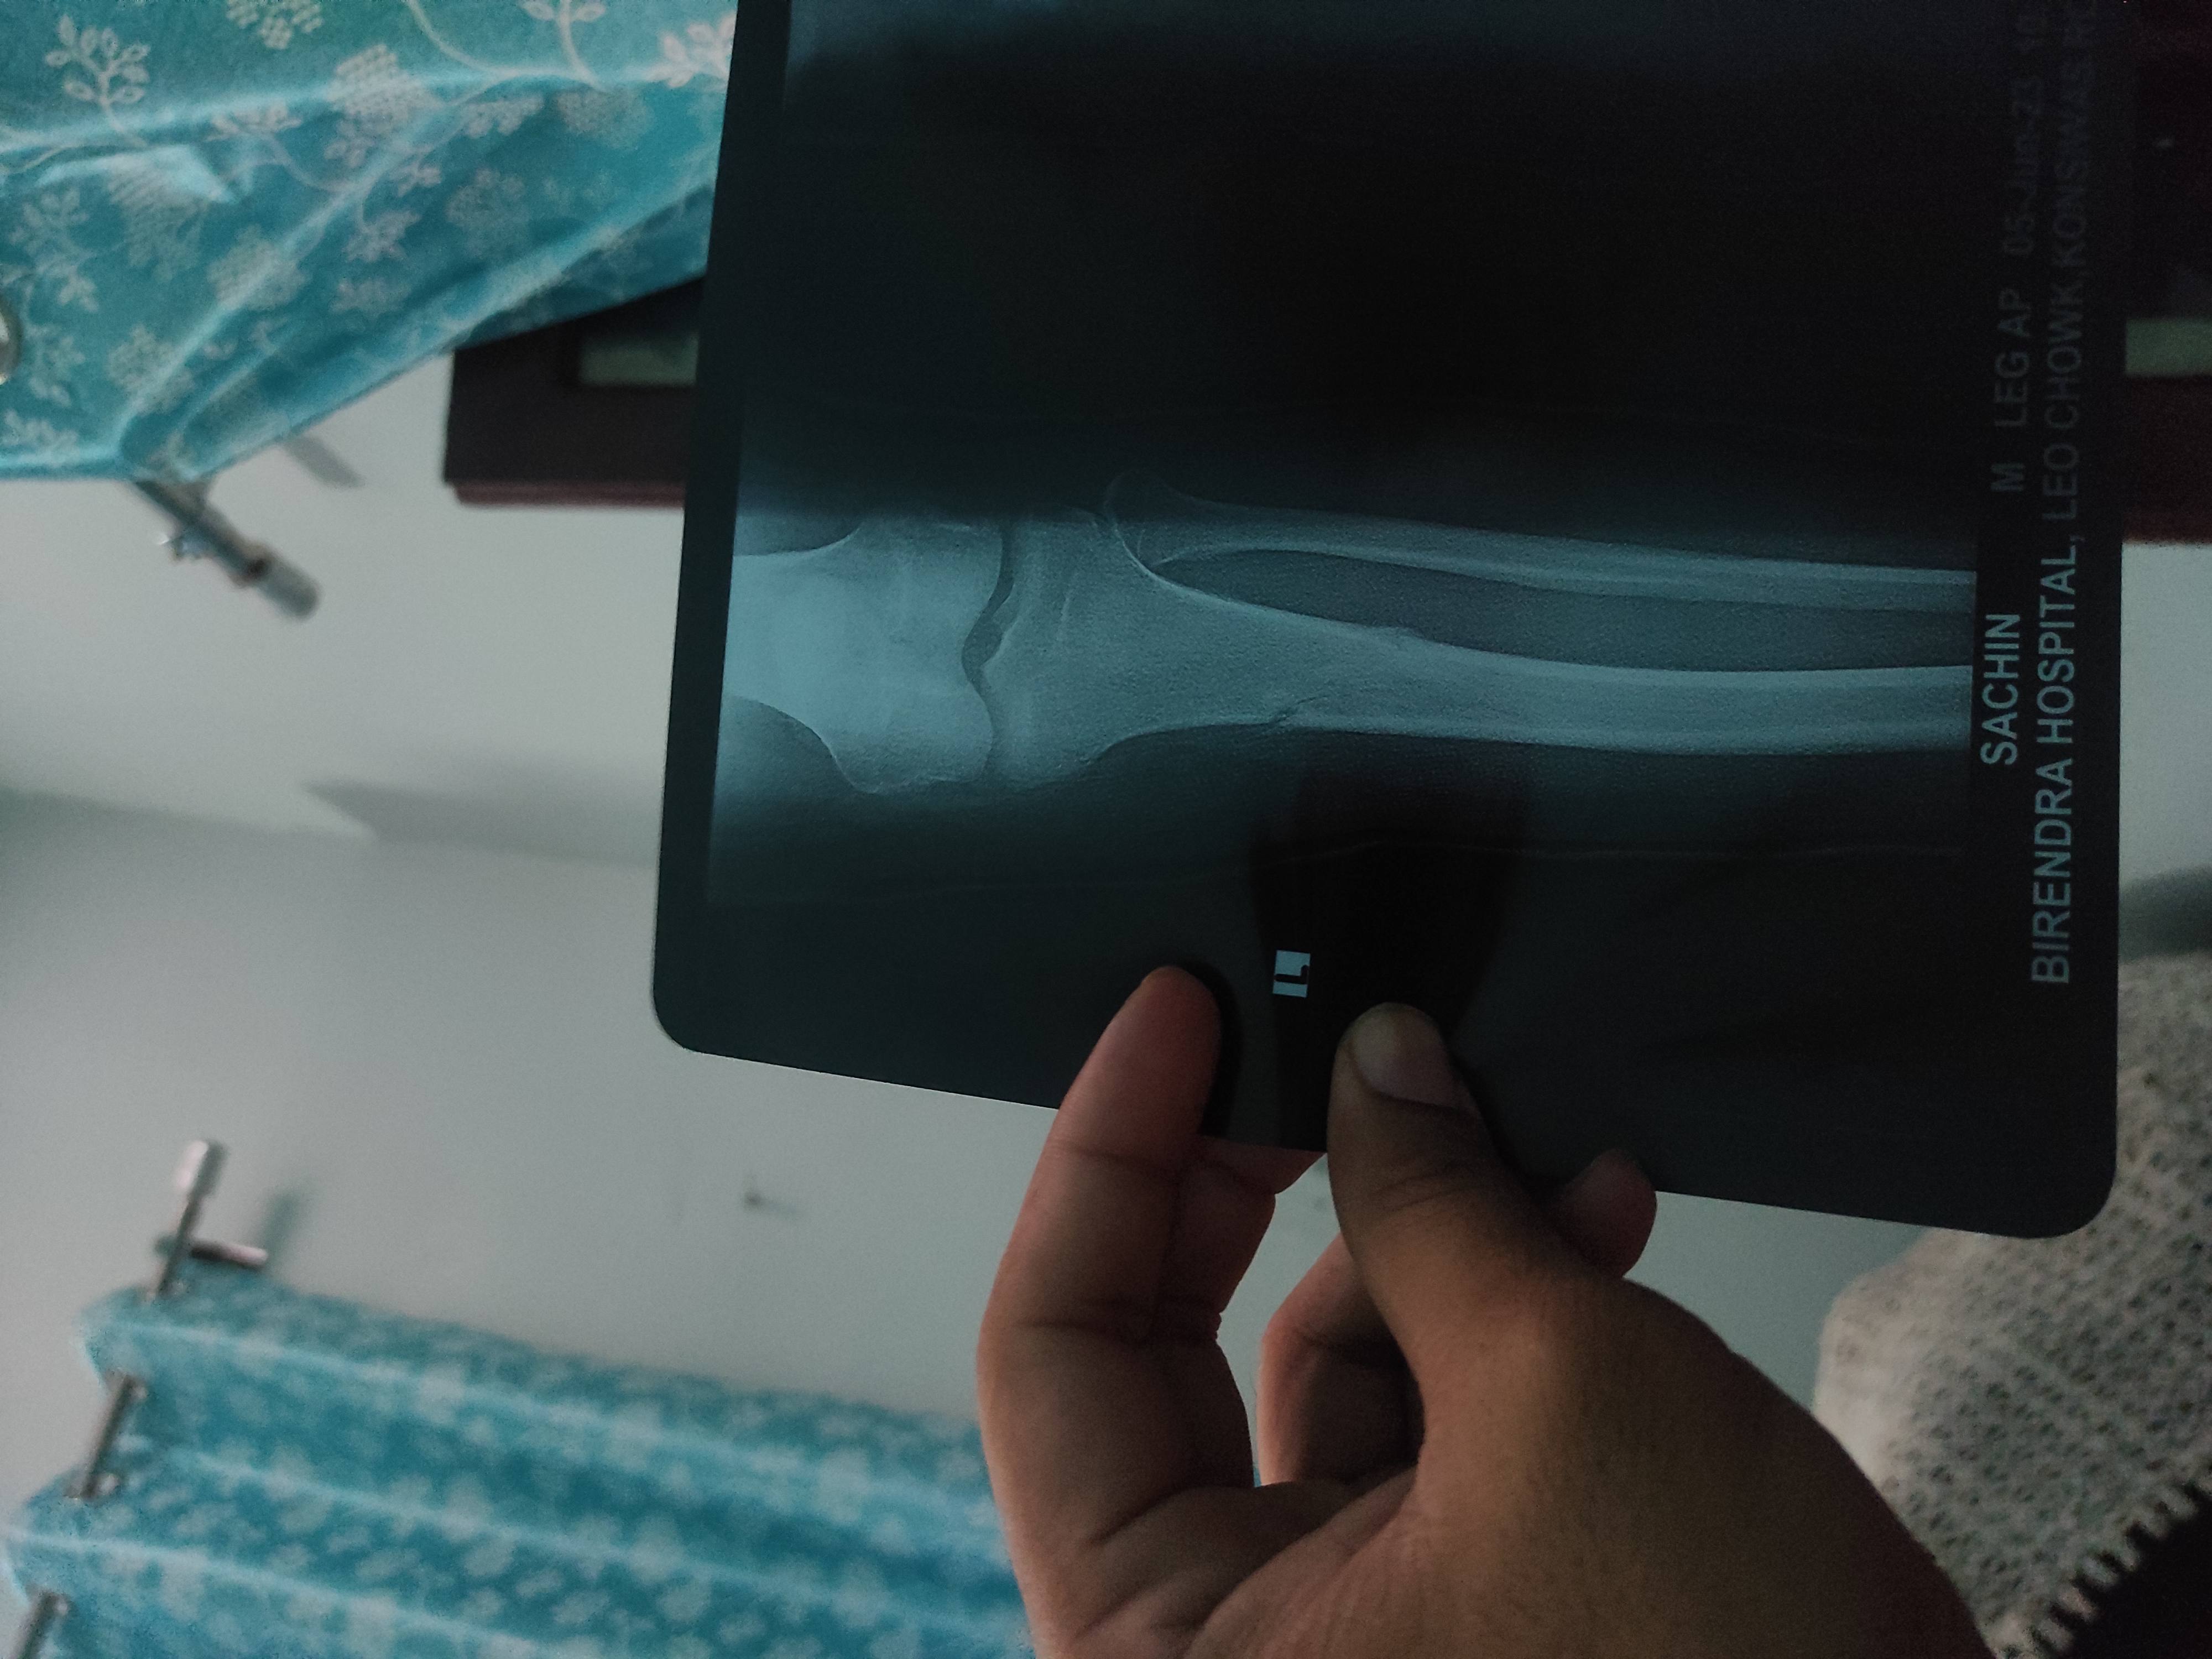

Sir i had got some fracture on hand and docs operate me on k-wire surgery on 14/06/23. Would you please suggest me for minimum how much time I'll remove those plaster and k wiring. As I have recently recruited for new job and I have to join it urgently